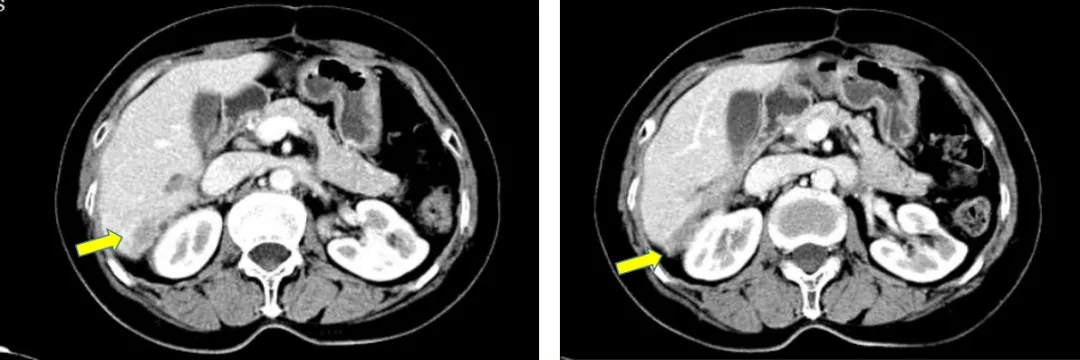

2019.5.8查CA125为78.3U/ml,CT显示右肝后缘欠光整伴片状低密度影。基因检测BRCA1致病性突变,诊断为铂敏感复发卵巢癌。2019.5-2021.4入组BGB-290-102单臂临床研究,口服PARP抑制剂治疗。

CT检查结果